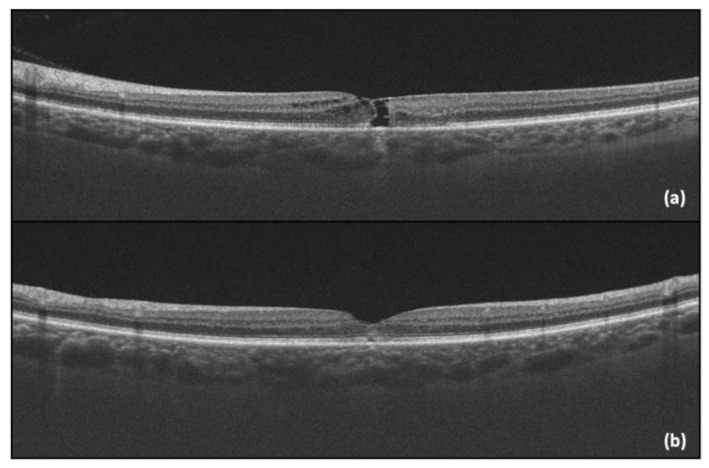

One year after the initial visit, there was a sudden drop in the LE BCVA (LE BCVA = 0.4), corresponding to the progression of the MacTel into a macular hole, with presented an “ILM drape” sign. Pars plana vitrectomy with an inverted flap technique was performed, with subsequent anatomical (OCT capture—Figure 4) and functional improvement (post-operative LE BCVA = 0.6).

Figure 4.

(a) LE OCT captured one year after the initial visit, showing the progression into a macular hole with a positive “ILM drape” sign; (b) LE OCT captured one month after vitrectomy.